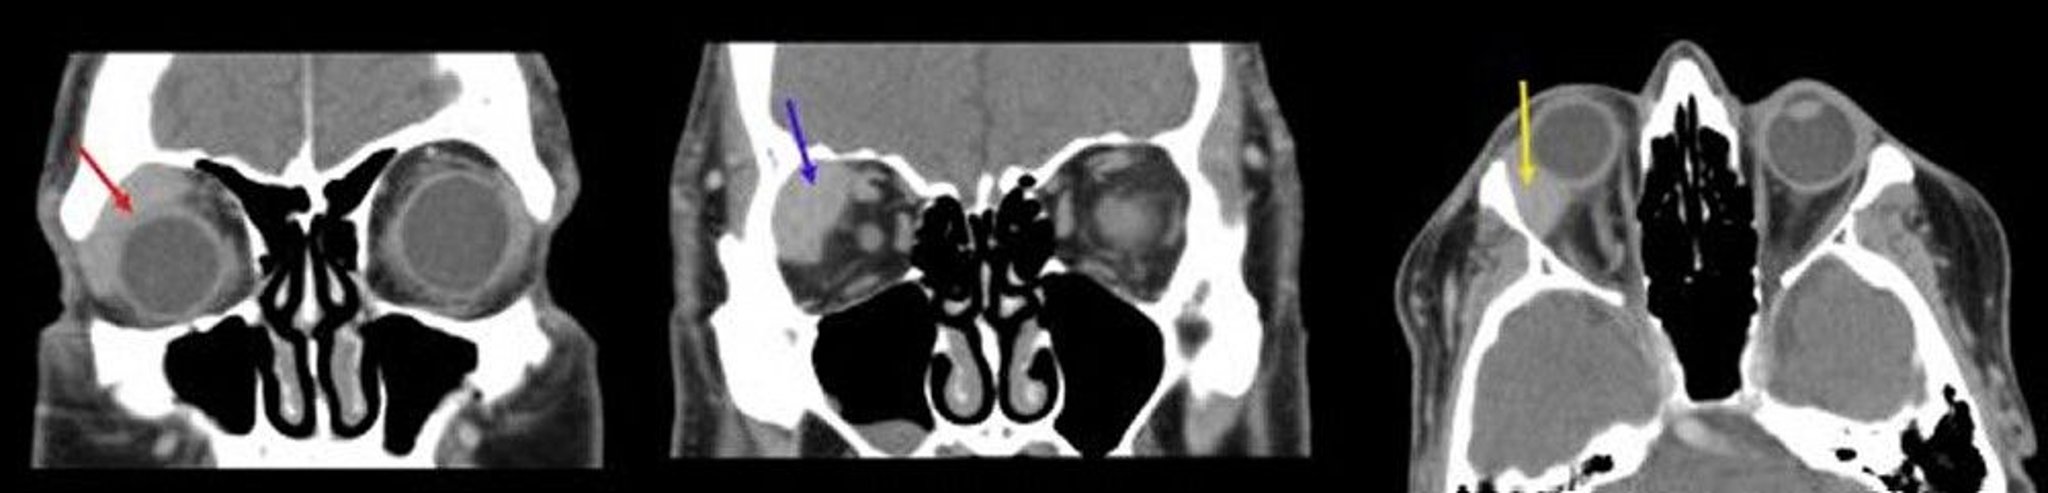

Orbital Lymphoma

In this image, the first coronal CT scan (left) shows a homogeneous mass conforming to the globe (red arrow). The second coronal CT scan (center) shows a well-demarcated mass in the right lacrimal gland fossa (blue arrow). The axial CT scan (right) shows a homogenous lacrimal fossa mass conforming to the right globe (yellow arrow).

Images courtesy of James Garrity, MD.